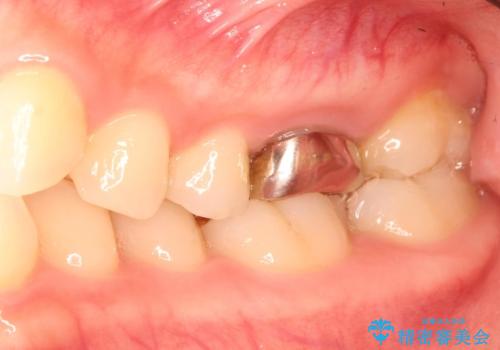

金属の奥歯 → 白い奥歯 根管治療からのやり直し

- 再根管治療→土台の築造 を行った上でのかぶせ物のやり替えをおこないました。

神経の無い歯のかぶせ物をやり替える際は、是非根管治療からしっかりやり直すことをおすすめします。

かぶせ物の種類:Bellezza